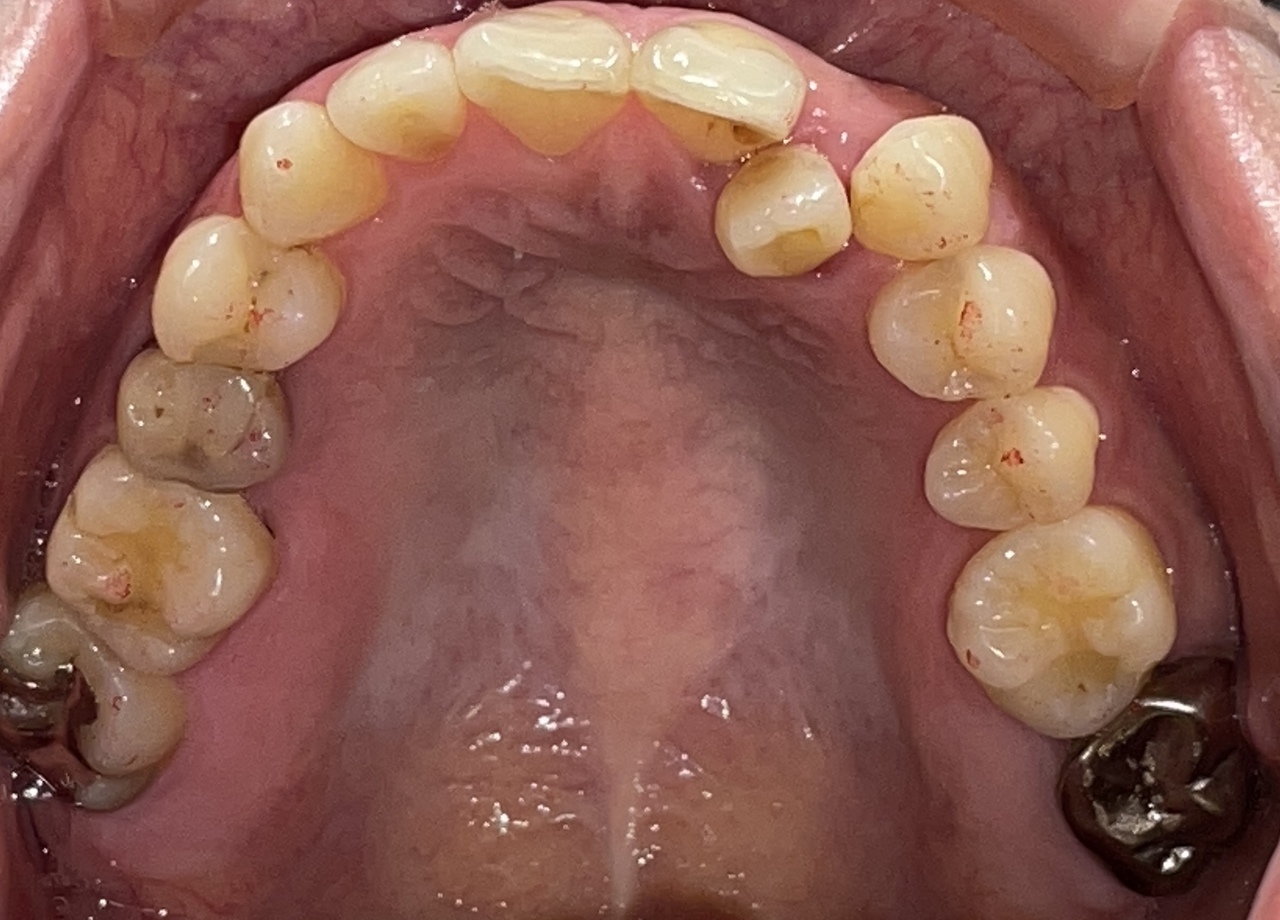

Before

After

矯正の種類 / invisalign GO

年齢・性別 / 30代男性

主訴  /  下の歯の叢生、オーバージェット、交叉咬合

治療期間 / 12ヶ月

費用 / 簡易検査 5,000円(税別) 精密検査 30,000円(税別)

両額マウスピース 450,000円(税別) 両額リテイナー料 40,000円(税別)

※マウスピース交換時別途調節料5,000円(税別)

副作用 / 口内炎・歯の移動に伴う痛み・知覚過敏 ※数日で収まる場合が多いです

リスク / 後戻り防止の為、夜のみマウスピースで保定を指示